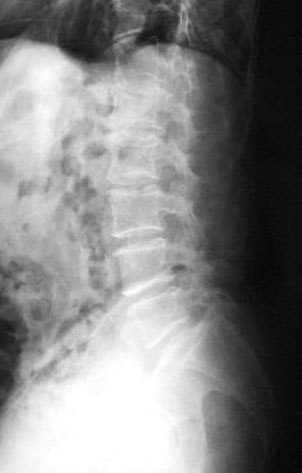

Osteoporosis. Cifosis.